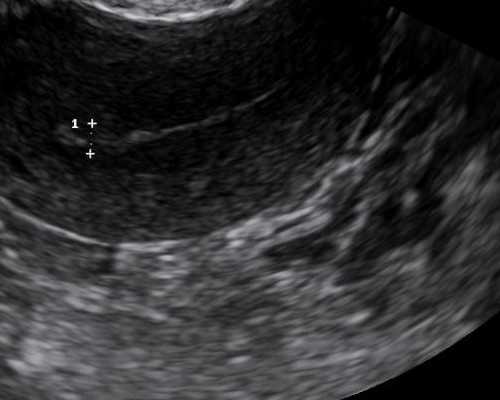

1、首先宝妈务必要等到孕期达到了7周或者7周以上,并且在当地的医院检测出胚芽长度达到了10mm,这是很必要的条件,谨记!

答:怀孕七周以上便能预约去香港抽血查验或者胚芽达到10毫米就可以检测的

1.必须胎龄满6周或以上,并且有注明已孕满6周或以上字样或者胚芽直径在10MM或以上的B超单。